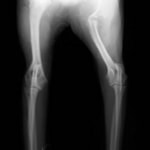

■ミニチュアダックスフント 1歳 去勢オス

前肢の成長板早期閉鎖、前肢の重度の外反変形が認められました。

関節面の変形が重度に認められます。